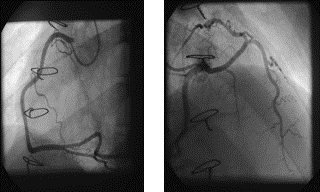

Figure 3.   Coronary Angiogram. The right coronary artery is shown in a 30 degrees RAO projection. The left coronary artery is shown in an RAO 25degresand Cranial 35 degrees projection.

The right coronary artery (RCA) is dominant and has no stenoses. The left coronary artery (LCA) has a long left main and some distal tapering of the LAD but no significant stenoses. The LCx was free of stenoses. There was aberrant origin of the LCA from the right coronary cusp. No evidence of transplant arteriopathy.